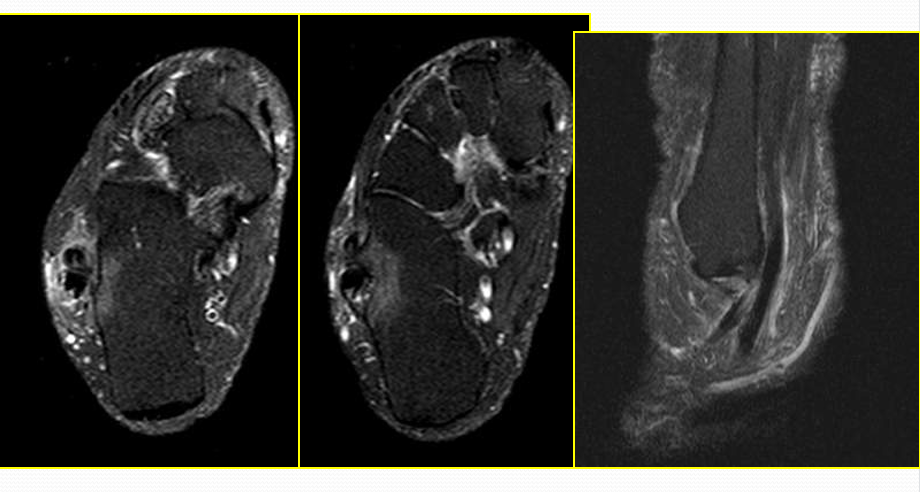

距腓前韧带撕裂

病因病理机制:

• 最脆弱的外侧韧带,也最先断裂

• 内翻内旋伴跖屈

• 距腓前韧带撕裂致内旋受限

• 临床表现为前外踝疼痛,活动受限